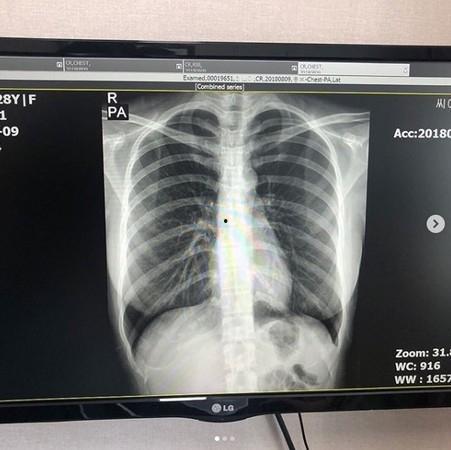

你知道吗,现在很多网红都开始晒自己的X光片了。他们把片子拍得美美的,然后配上各种有趣的文字,瞬间吸引了大批粉丝的关注。有的网红晒出了自己的骨骼结构,有的则晒出了自己的牙齿排列,还有的甚至晒出了自己的肺部情况。这究竟是为了什么呢?